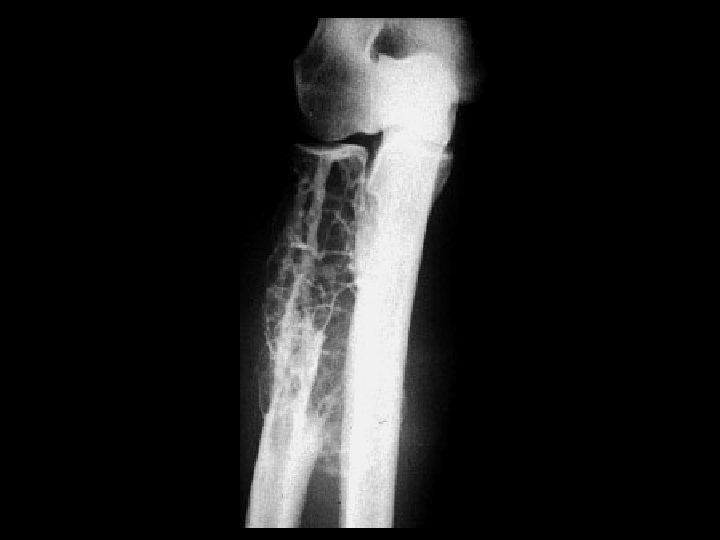

Aneurysmal Bone Cyst • Findings: – expansile lytic lesion of the distal ulnar metaphysis – well-defined margins – internal septations – No periostitis • A result of trauma or tumor induced process • ddx: – Giant cell tumor – Chondroblastoma – Osteoblastoma – Fibrous Dysplasia – lytic met

Metastatic Renal Cell • • • Findings: – expansile lytic lesion of the distal ulnar metaphysis – well-defined margins – internal septations – No periostitis Don’t forget about mets! ddx: – ABC – Giant cell tumor – Chondroblastoma – Osteoblastoma – Fibrous Dysplasia